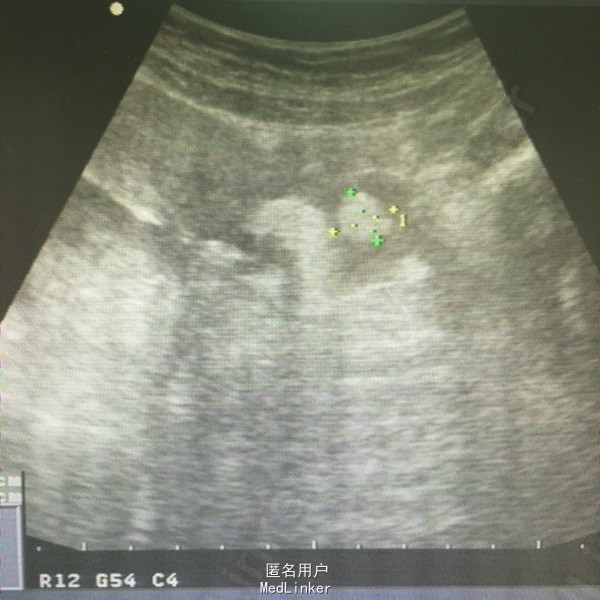

肛查:双侧附件区个扪及一肿物,右侧6*6cm,无压痛、反跳痛,左侧3*3cm,有压痛,无反跳痛。阑尾彩超未见明确显示。血常规白细胞及中性粒细胞百分率升高。彩超子宫双附件:双侧附件区混合性肿块,右侧60*54mm,左侧38*21mm,呈面团征,后方回声增强,考虑畸胎瘤可能性大。

诊断:双侧卵巢畸胎瘤,左侧卵巢蒂扭转。行腹腔镜检查,术中见右侧输卵管扭转180°,卵巢表面血运良好,予行双侧卵巢囊肿剔除,标本中查见毛发及油脂。术后病理:双侧卵巢成熟性畸胎瘤。